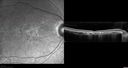

59-year-old man has macular dystrophy in both eyes. He saw Dr. Gass in 1989, at which time Dr. Gass thought it might be post inflammatory. Interestingly, at this point he still does not have a diagnosis other than macular dystrophy. His vision since he was here last is reasonably stable.

He has been diabetic for eight years. He had LASIK surgery done in 1998. He was a high myope, about a -10 and now he is about a -3. He had some vision changes in medical school in the 1980s and saw Dr. Gass for that. He had some pigment epithelial irregularities in both eyes. Dr. Gass felt maybe this was an atypical case of previous AMPPE. Otherwise he is in good health. He had strabismus as a child and had muscle surgery. He is color blind, along with many people in his family, and as far as he knows, it is congenital.

VISUAL ACUITY: Vision OD is 20/25, OS is 20/30. IOP: OD 14, OS 13. The lenses are clear.

OD: Vertical C/D ratio is 0.2. There are no vitreous cells. The retinal vessels are slightly attenuated. The retina is very thin looking.

OS: Vertical C/D ratio is 0.2. Again, the retinal vessels are attenuated. The retina does appear to be thin looking.

OCT SCAN: The OCT scan shows retinal atrophy in both eyes.

1. RETINAL ATROPHY – BOTH EYES